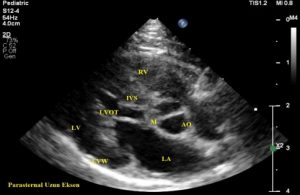

Civelek, bu vakaya, kendisinin lisansüstü danışmanlığını yürüttüğü veteriner hekimler Ender Erkoç ve Cankan Alpay’ın kliniklerinde, tekir ırkı erkek bir kedide rutin kalp ultrasonografisi (ekokardiyografi) sırasında rastlandığını ifade ederek, şu bilgileri verdi:

”Kesin tanı için bizden destek istediler. Görüntüleri incelediğimizde bunun nadir gözlenen bir tümör olabileceğini gördük. Olayı tanımladık ve bilim dünyasına kazandırdık. Kalp hastalıklarına her yaştaki kedi ve köpeklerde sıklıkla rastlanmaktadır. Kardiyak tümörlere ise kedilerde nadir rastlanır. Bu tümörlerin teşhisi genellikle ekokardiyografik muayene yani kalbin ultrasonografisiyle yapılır. Sunulan vakadaki ‘papillar fibroelastoma’ primer bir kalp tümörüdür ve iyi huylu olarak bilinir. Bununla birlikte, bu tip tümörler tromboemboli (pıhtı atma) riski taşır, felç ya da enfarktüs gibi komplikasyonlara sebebiyet verebilir. Bu tip olgulardaki belirtiler net değildir ve kitlenin boyutu veya yapısıyla bağlantılı olarak değişkenlik gösterebilir.”